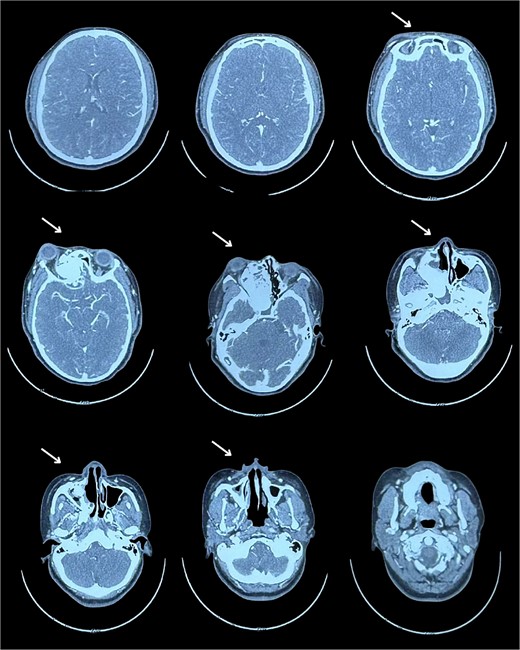

A tomography was performed to assess the extent of the mass inside the right nasal cavity. The imaging findings (Fig. 1) were consistent with a large mass (65 × 44 + 39 mm) originating from the right turbinates that was heavily remodeling the medial wall and the floor of the right orbit, compromising internal aspects of the maxillary and ethmoid bones; leading to a superior lateralization of the right eye causing exophthalmos.

Muscular and neural tissue were conserved intact but displaced.